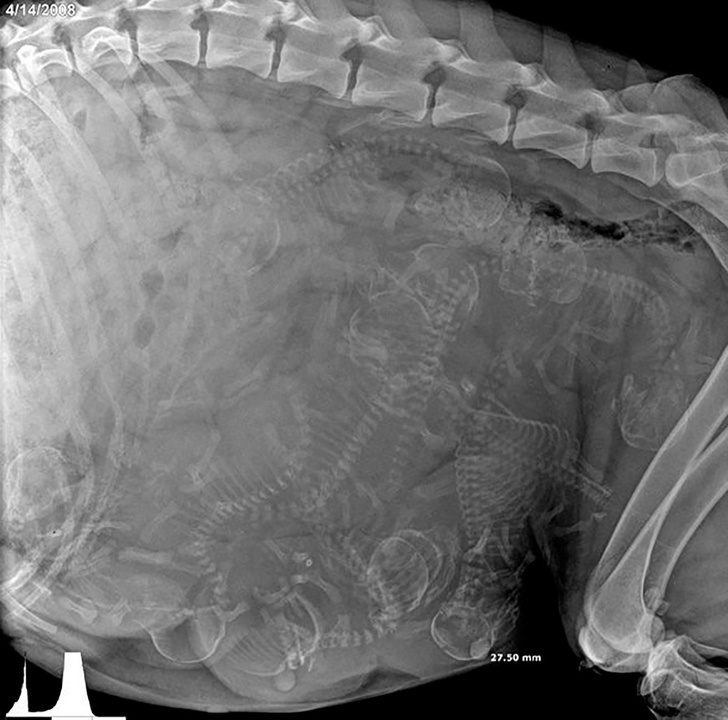

▼7. 看看懷孕狗媽媽的肚子裡長怎樣!